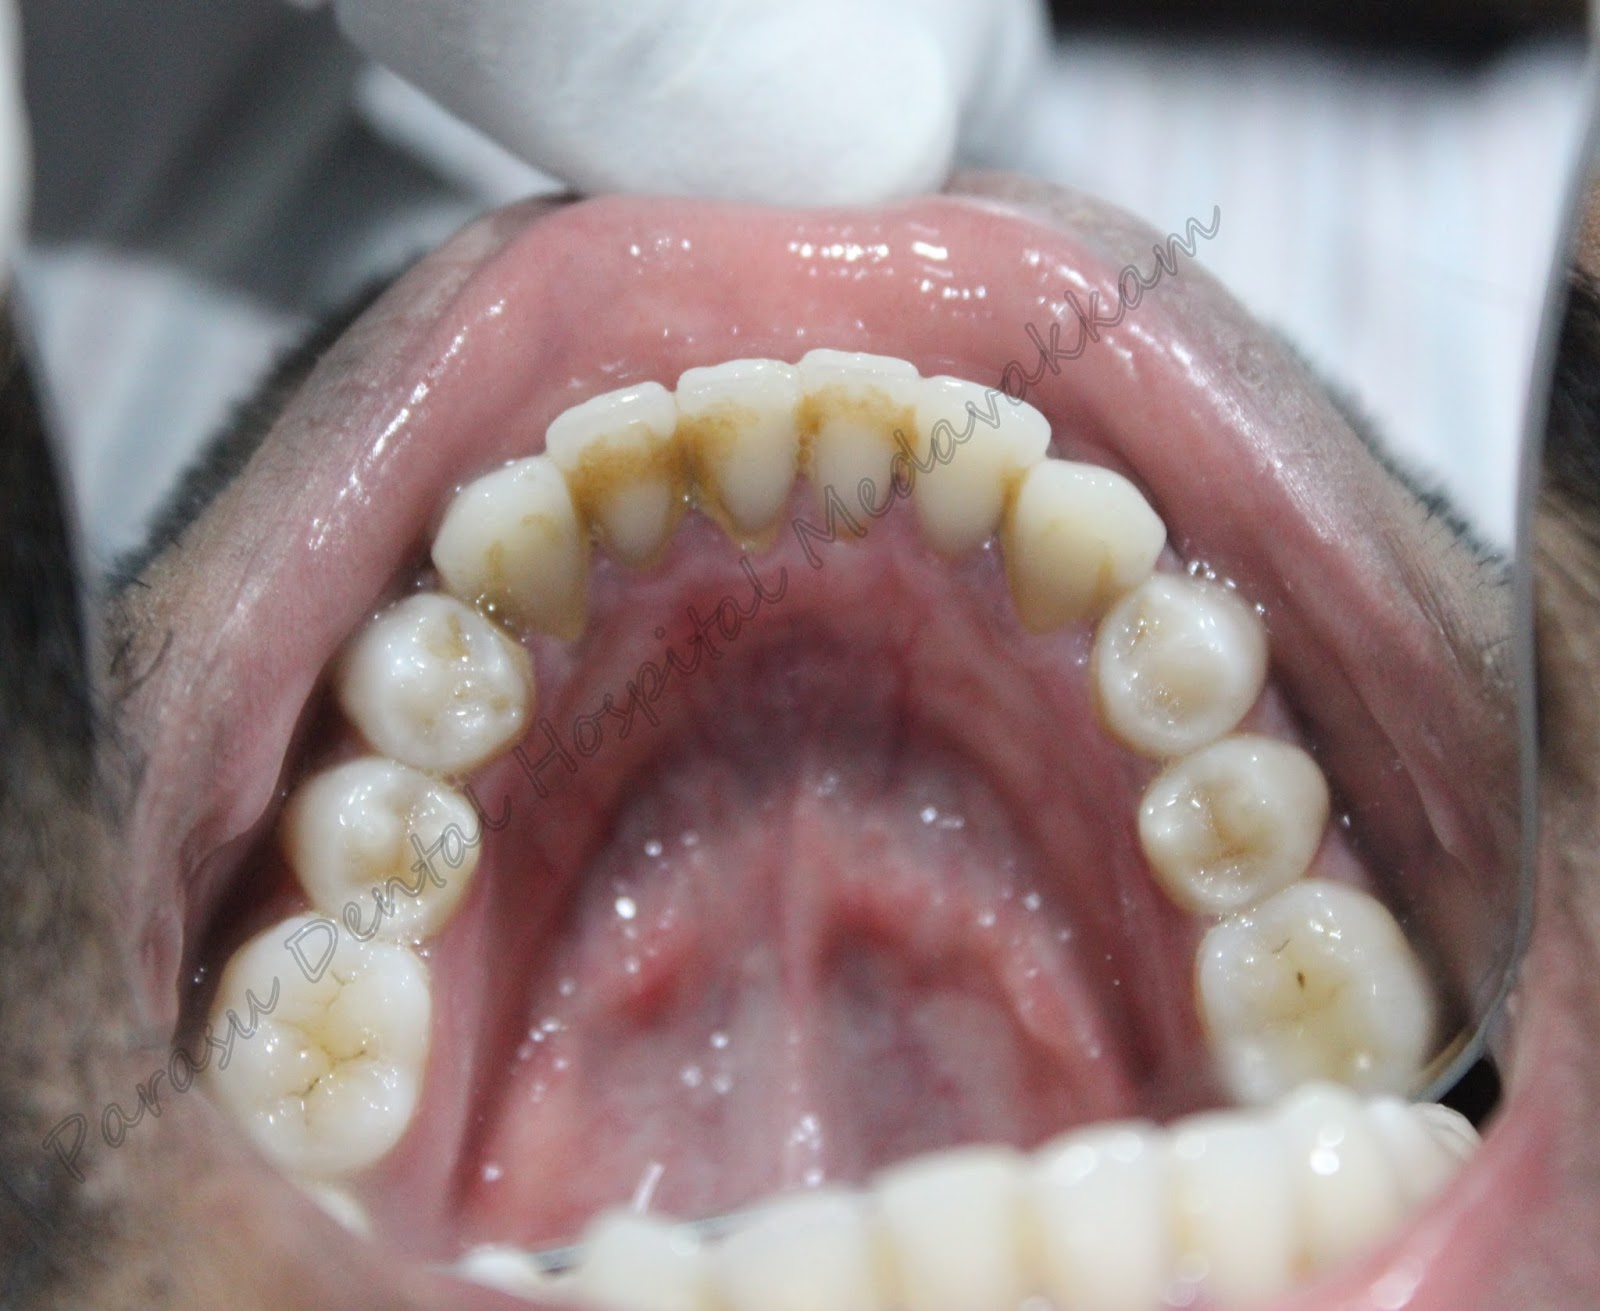

Patient came with the complaint of deposits in his teeth and also bad breath